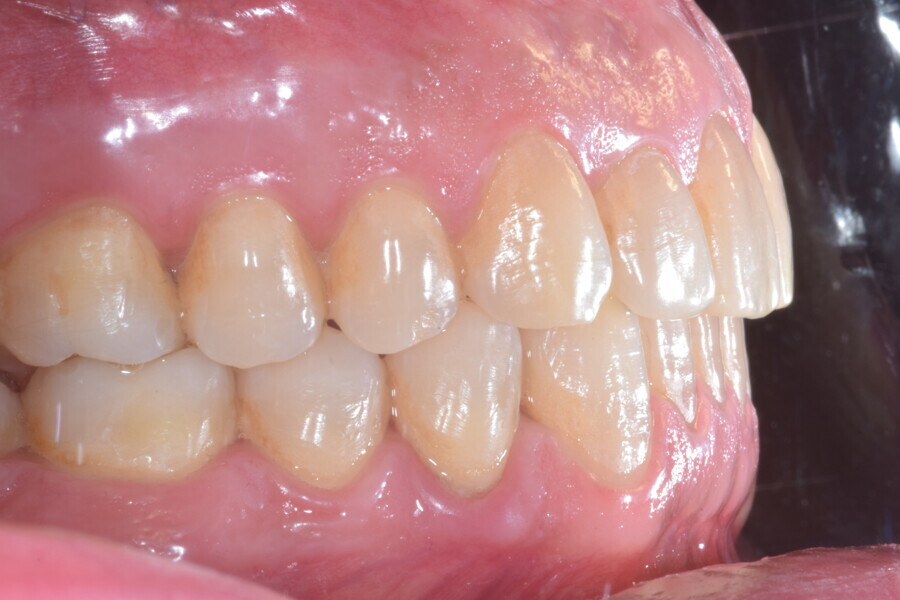

Le plan de traitement numérique (ClinCheck) avait prévu douze aligneurs pour l’arcade maxillaire et dix-sept pour l’arcade mandibulaire. Les objectifs du traitement visaient à combiner les mouvements verticaux d’extrusion des dents postérieures et les mouvements d’intrusion des dents antérieurs, au moyen de rampes d’occlusion, tout en utilisant des taquets d’extrusion pour assurer la désocclusion des dents postérieures et l’intrusion des dents antérieures inférieures, nécessaires au nivellement de l’arcade mandibulaire. La courbe de Spee a été nivelée et le profil plat ainsi que la position des lèvres ont été améliorés par une vestibulo-version des incisives supérieures et inférieures. Le plan avait prévu des élastiques de classe II pour faciliter la vestibulo-version des dents inférieures et les puissants contacts occlusaux postérieurs, avec une extrusion relative des dents postérieures. Une morphologie plus large de l’arcade et une intercuspidation idéale ont été obtenues par des mouvements de torque proches de 0° des dents latérales et postérieures supérieures. Aucune conception technique excessive n’avait été prévue dans le plan de traitement numérique. En raison de l’âge du patient, les aligneurs ont été changés tous les dix jours, dans le cadre d’un traitement d’une durée inférieure à six mois. À la fin de la première série d’aligneurs (Figs. 20–24), un nouveau plan de traitement numérique comportant cinq autres aligneurs a été conçu, en vue d’améliorer l’intercuspidation des molaires sans élastiques. La durée totale du traitement a donc été prolongée jusqu’à 7,5 mois puisque les aligneurs supplémentaires étaient changés toutes les semaines.

À la fin du traitement, on pouvait observer une relation de classe I des canines et des molaires, une légère augmentation de l’inclinaison des incisives supérieures (Ui-FH = 112°), une correction complète de l’inclinaison des incisives inférieures (IMPA = 97,09°) grâce à la vestibulo-version, et une légère amélioration de l’hypodivergence (SN-GoGn = 27°) résultant de l’extrusion relative des dents postérieures, et de l’utilisation d’élastiques de classe II — petite variation (1°) très intéressante compte tenu de l’âge du patient (Figs. 25–35). La ligne du sourire était harmonieuse et correspondait à une relation idéale entre les incisives supérieures et la lèvre inférieure. Le sourire avait été élargi grâce au contrôle du torque des segments latéraux et postérieurs.

Lors du suivi à un an, alors que le patient portait un appareil de rétention (appareil de rétention Vivera avec rampes d’occlusion, Align Technology), le résultat était stable et l’intercuspation était nettement meilleure (Figs. 38–42).